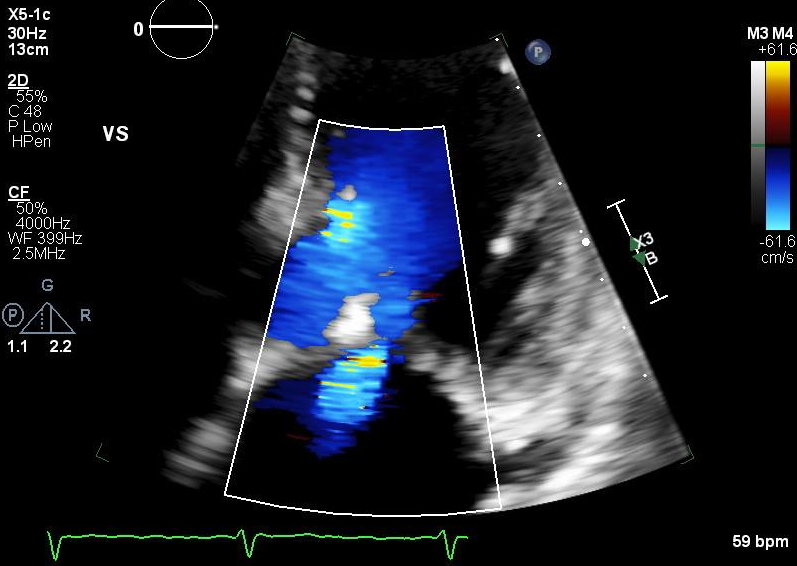

12 weeks after initiation of mavacamten, surveillance TTE demonstrated a LVOT gradient of 7 mmHg at rest and 11 mmHg during Valsalva maneuver, and a basal septal wall thickness of 1.0 cm. Severe mitral regurgitation was noted with the mechanism identified as both Carpentier type I and II. The primary etiology of the regurgitation was determined to be P3 prolapse (Figure 2). There was no longer evidence of SAM.